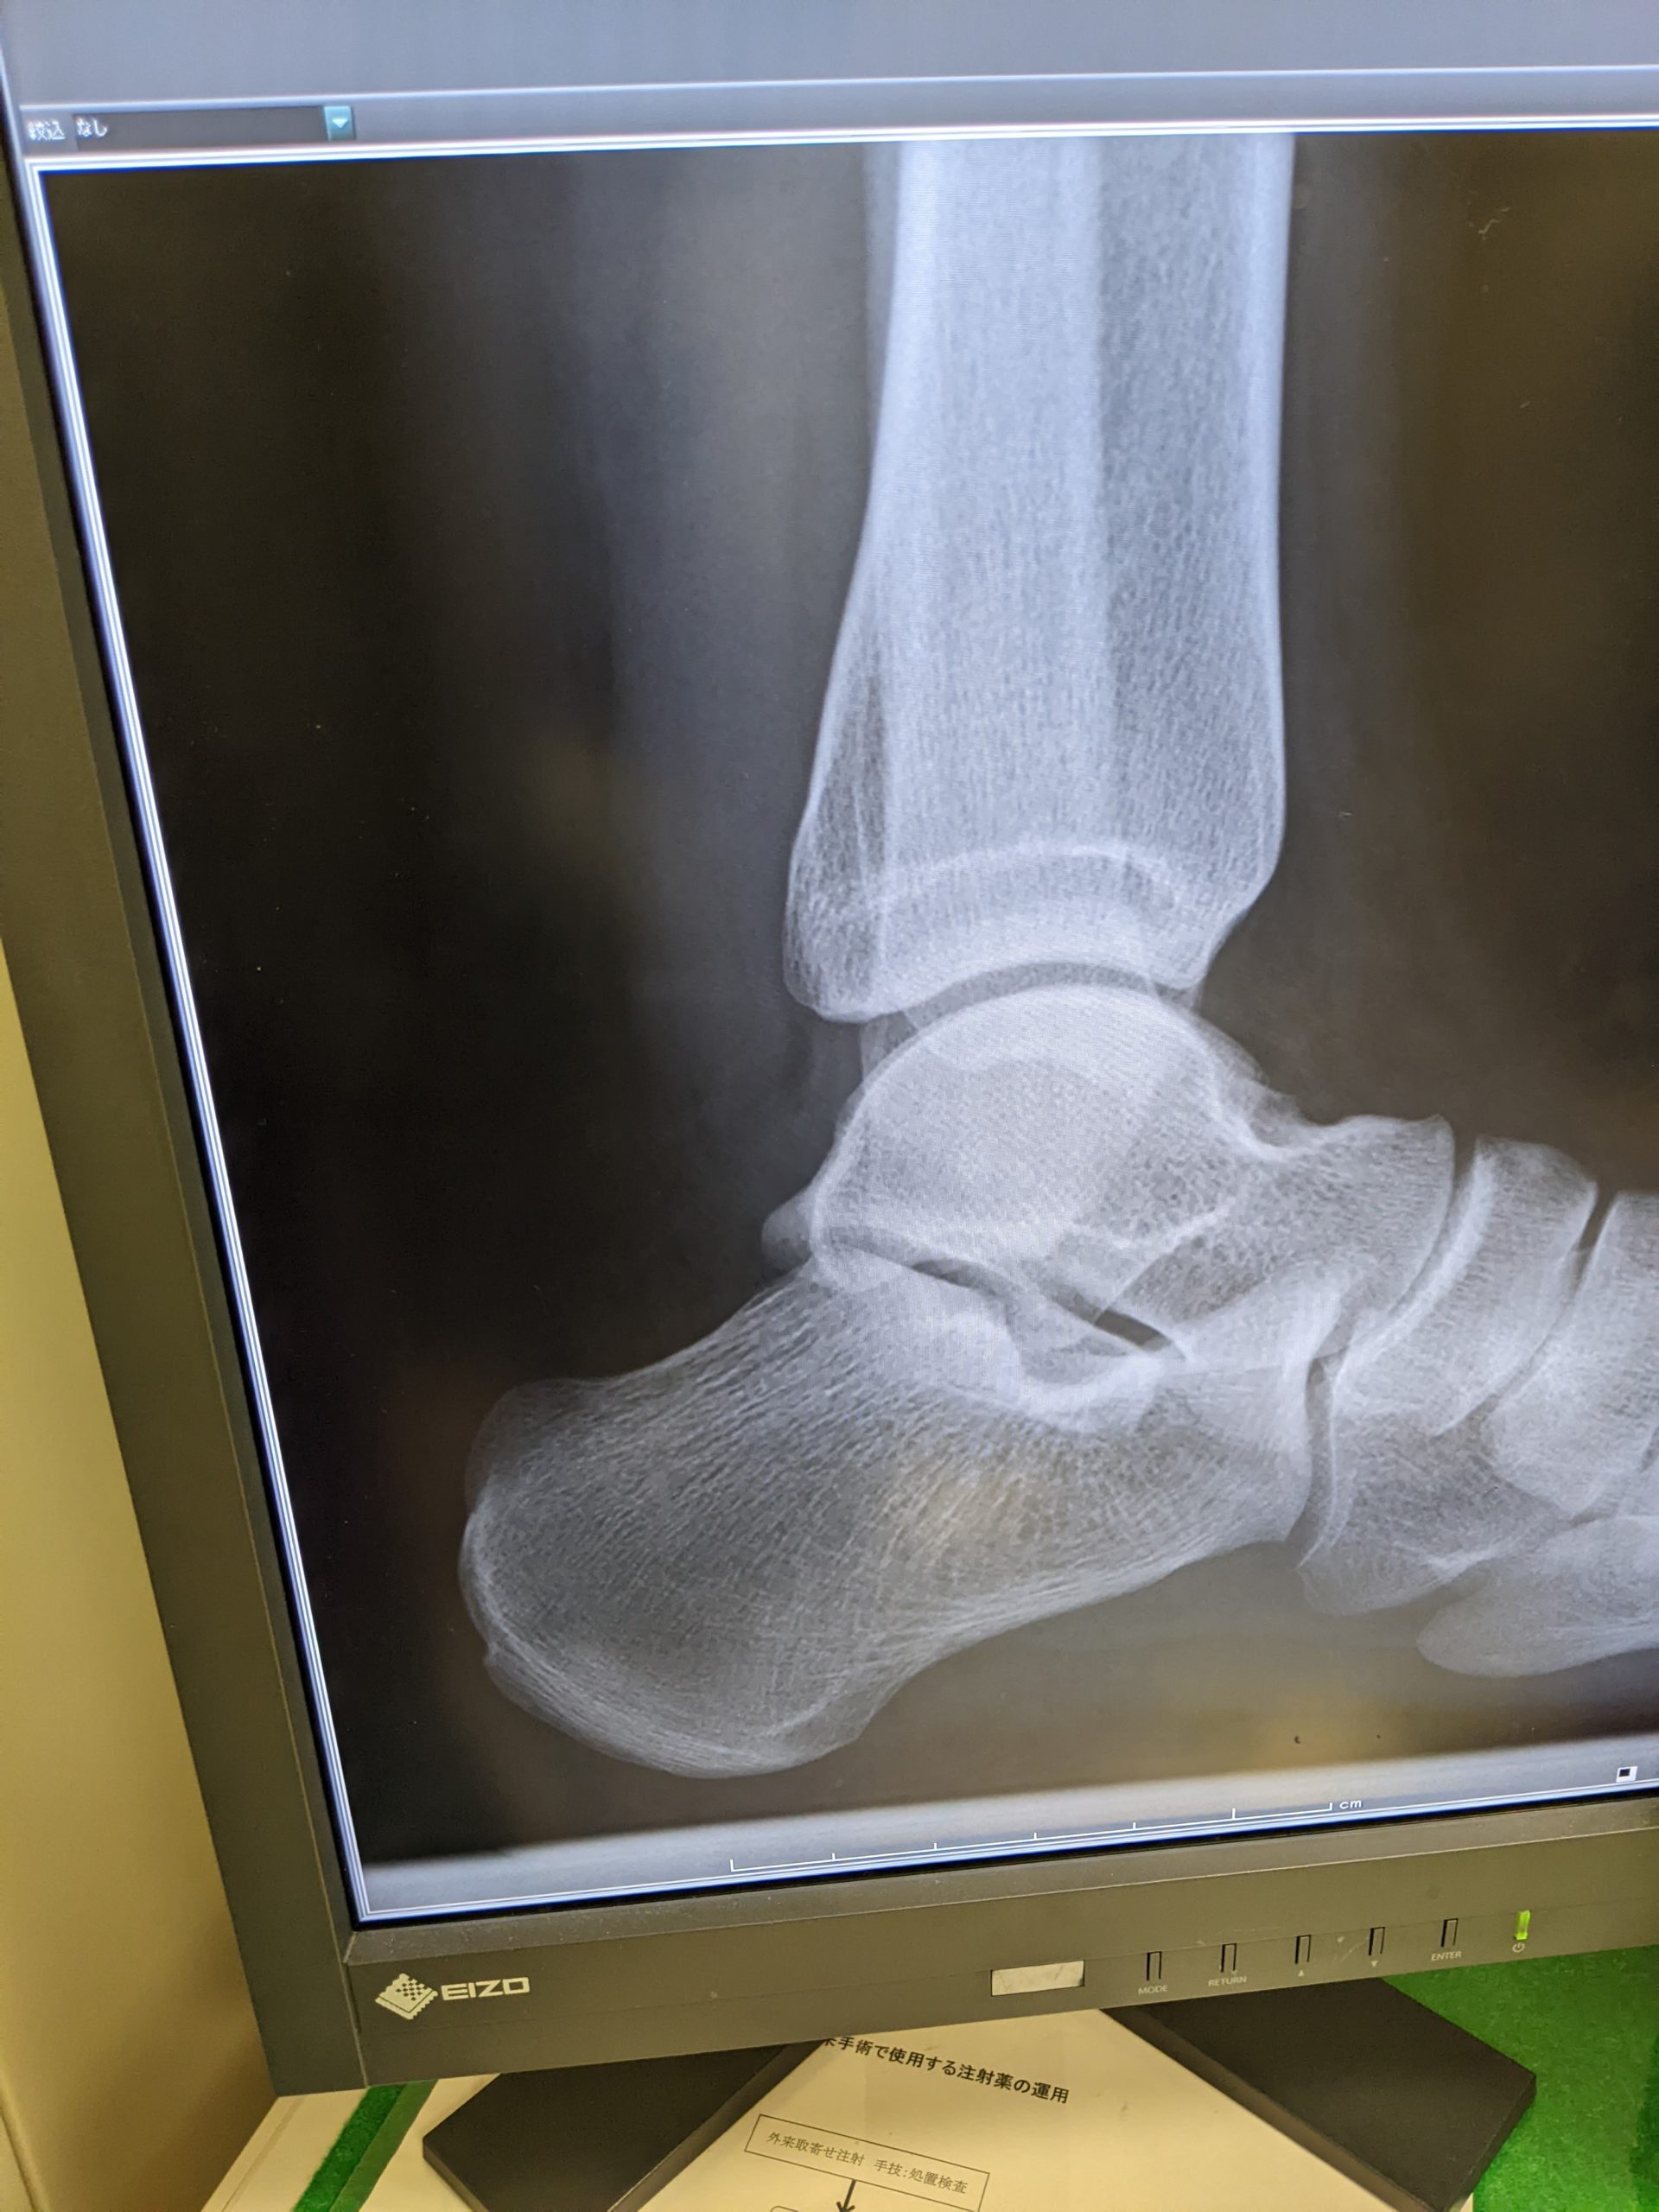

診察を終え 後方インピンジメント症候群と診断された 余剰骨が過形成し挟まって痛みが出る疾患だ。

鍼で骨は消せない。。 そら痛いわな。と思った。

僕は医師に根掘り葉掘り聞いた。 どう診断するのかとか。 オペしかないと言われた。

画像は患者さんからの許可あり。